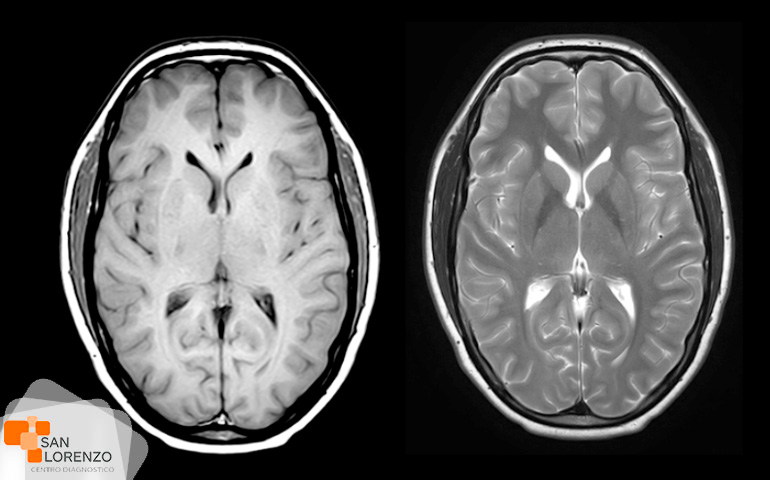

Algunos de los exámenes relacionados con medios de contraste son: Angiotac, Urotac, TAC de abdomen y pelvis, TAC de cerebro en lo que se solicite contraste, y todas aquellas Resonancias magnéticas contrastadas.

¿Para qué tipos de exámenes se aplica la medición de la creatinina? ¿Podemos mencionar los exámenes? Todos los exámenes de RM, TAC que requieran contraste tal como los mencionados anteriormente: Angiotac, Urotac, TAC de abdomen y pelvis, TAC de cerebro en lo que se solicite contraste y todas aquellas Resonancias magnéticas contrastadas.

¿Qué es un Escáner (TAC)? ¿Qués es una Resonancia magnética? Cotizar examen